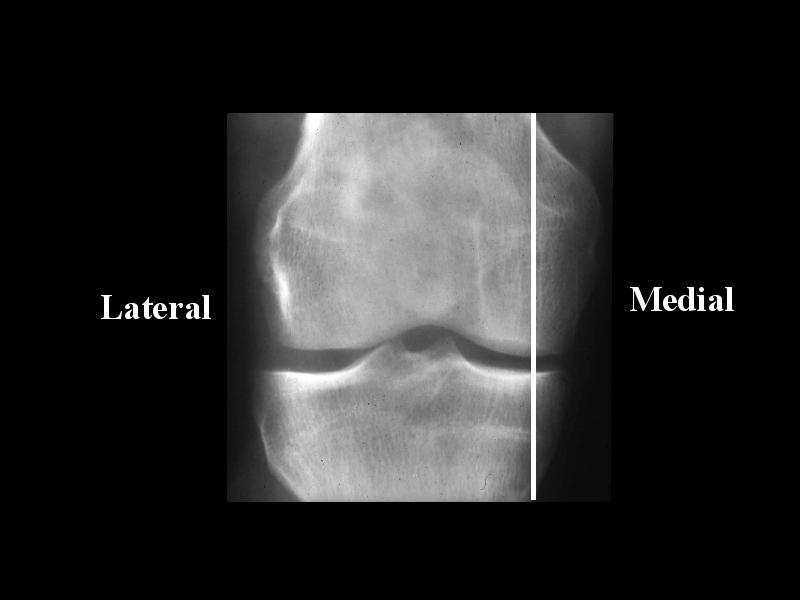

1900759 AP KNEE